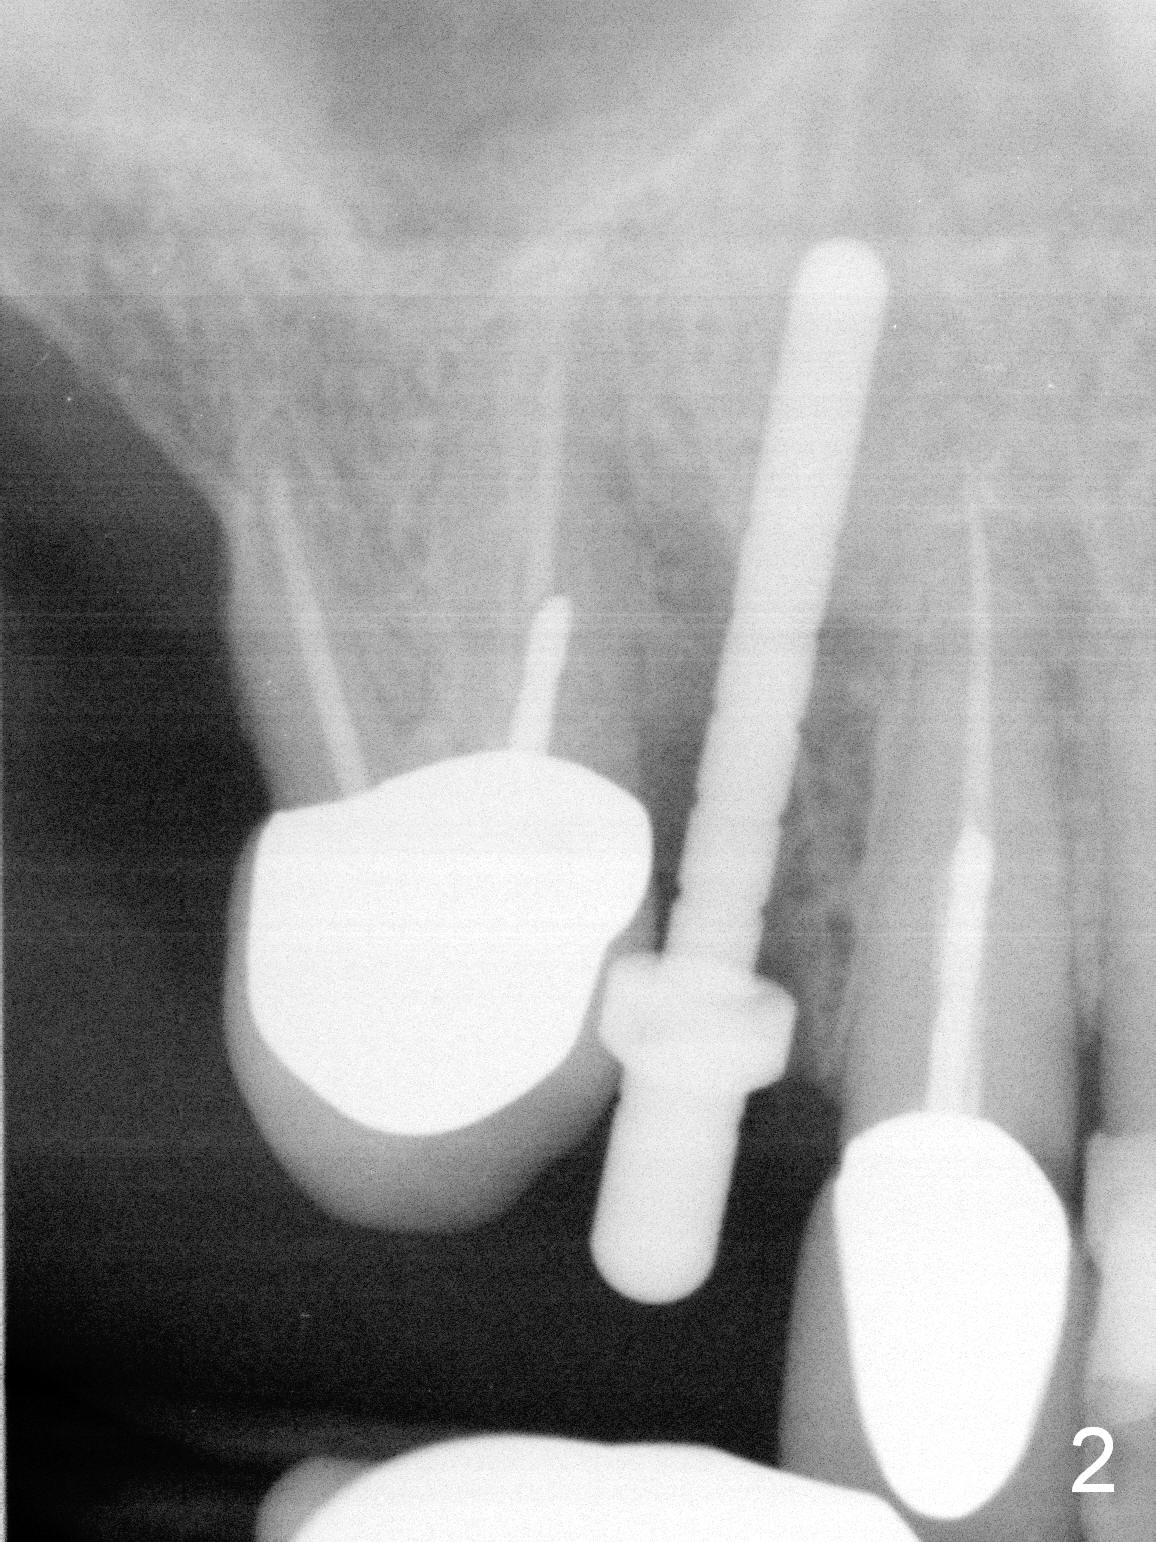

After extraction of the subgingival fractured upper right canine (Fig.1), the buccal plate is found to have been perforated at the apex. the root is measured 5x12 mm. Initial osteotomy with a 2 mm pilot drill shows that the bone is soft (Fig.2). After use of a 3.2 mm drill (underprep, normal drill size (3.7 mm)), a 4.5x15 mm implant is placed with insertion torque > 50 Ncm (Fig.3). The implant is further torqued until the implant plateau is 3 mm apical to the buccal gingival margin; a 5.5x5(3) mm abutment is placed (Fig.4,5 A). Osteogen plug is inserted into the apex of the socket, while the rest of gap is filled with mineralized cortical allograft and Osteogen. An immediate provisional (Fig.5,6 P) is fabricated to keep the graft in place, followed by periodontal dressing (Fig.6).